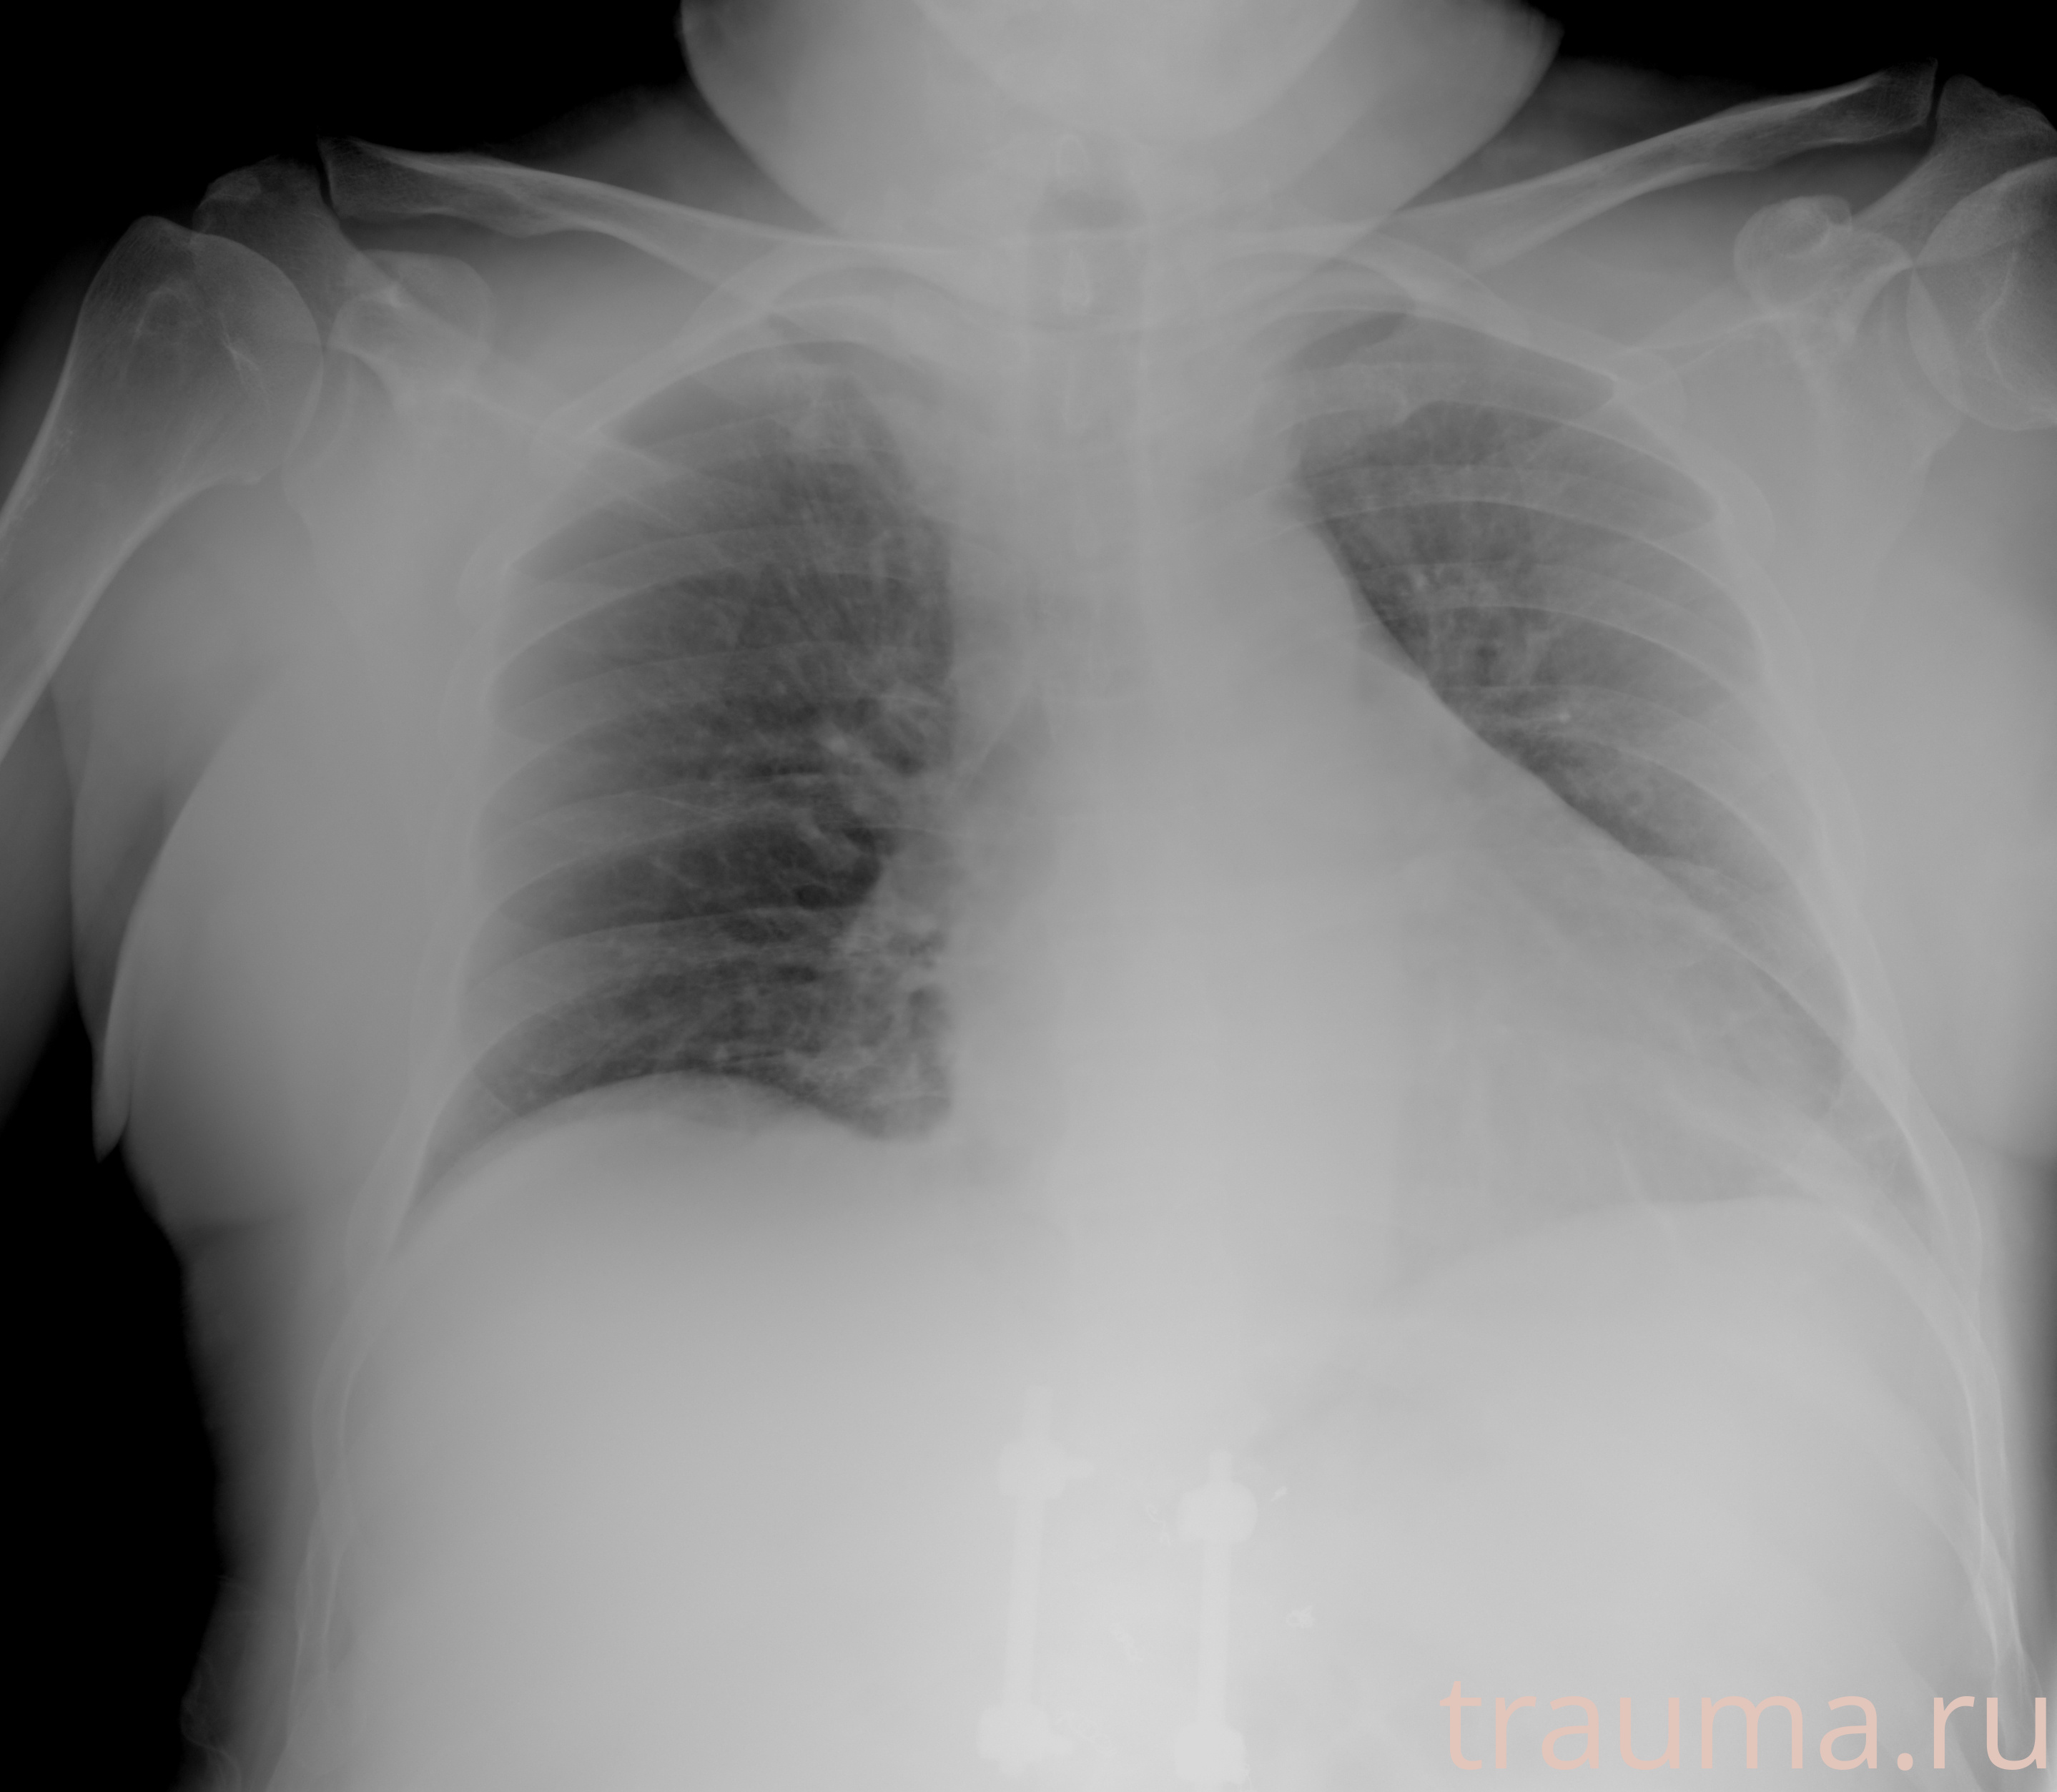

Рентген на дому: по вашему адресу приезжает врач-рентгенолог, травматолог-ортопед с мобильным рентгеновским аппаратом, проводит диагностику травмы или заболевания, делает необходимые рентгенограммы, дает рекомендации по дальнейшему лечению. Получить качественные снимки в домашних условиях возможно благодаря уникальной методике, разработанной МосРентген Центром для института  Склифосовского